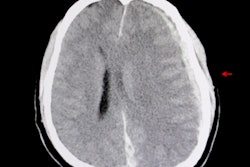

The team found that the video motion analysis algorithm they developed had an 87% accuracy rate of detecting stenosis in 109 study participants known to have carotid artery stenosis. The algorithm analyzes smartphone video recording, using motion magnification and pixel analysis to detect changes in pulse characteristics on the neck skin's surface.

All study participants also had standard Doppler ultrasound testing to confirm narrowing in their arteries, as well as validating the estimates from the video motion analysis.